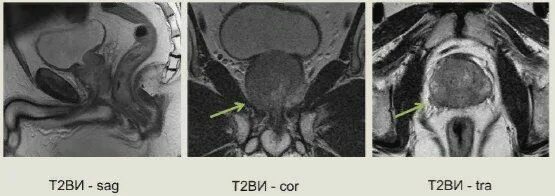

Перед мрт простаты